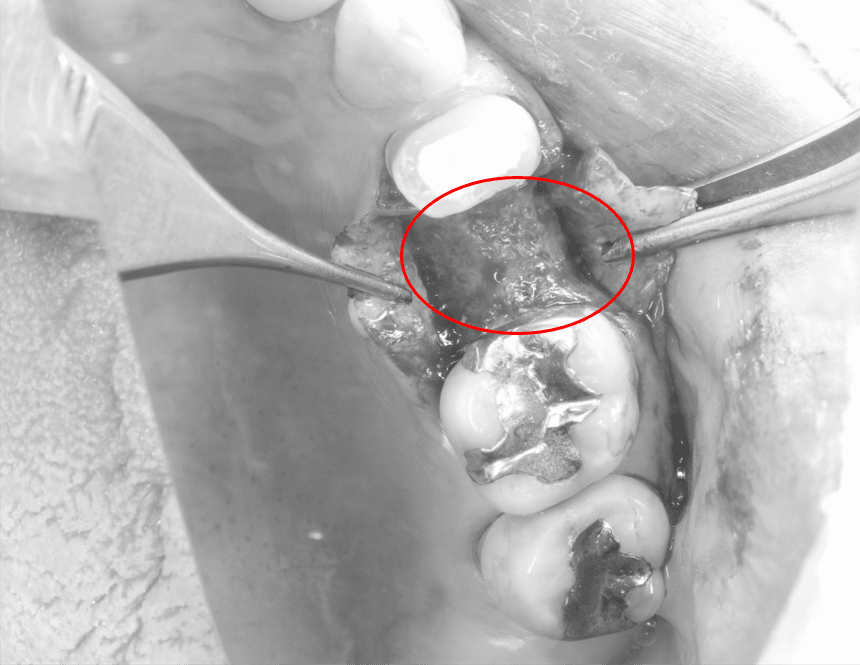

オペ中⇓

○印の部分が造骨処置を行い、骨が出来上がったところです。

○印の骨の部分に十分な厚みを確保した状態で、埋入することができました。